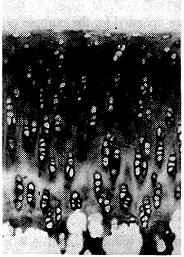

韧带无张力组膝关节软骨细胞排列无规律,甲苯胺兰染色可见基质染色不均,尤以中间层及柱状层为著。细胞周围较对照组染色重,而远离细胞部位明显变浅,有个别基质区甚至完全不着色。细胞有簇集现象,偶见细胞分裂相。见图2。

韧带有张力组,膝关节软骨细胞排列无规律,基质染色不均,其特点基本同上述。细胞有簇集现象。见图3。

图2.韧带无张力组:术后5天,软骨细胞排列紊乱,细胞有簇集,基质染色不均。甲苯胺兰×100

Fig.2Exp group. MCL no tension:5 days after operation disorder of chondrocytes arrangement,cell cluster,matrix stained unevenly. Toluidine blue×100

图3.韧带有张力组:术后5天,软骨细胞排列紊乱,细胞有簇集,基质染色不均。甲苯胺兰×100

Fig.3Exp group. MCL in normal tension:5 days after operation disorder of chondrocytes arrangement,cell cluster,matrix stained unevenly. Toluidine blue×100